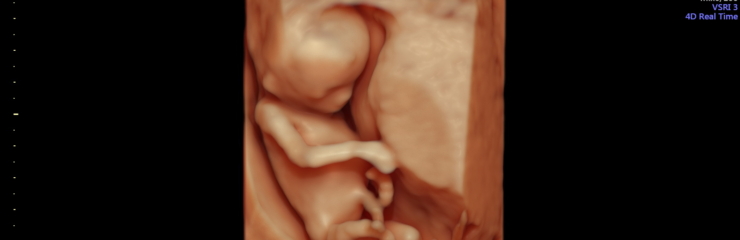

Loode:

Loote sõrmed ja varbad on sel ajal eristatavad. Pea moodustab peaaegu poole loote suurusest. Võrreldes 7. nädalaga on 10. nädalal loote kaal kahekordistunud. Kujunema hakkavad sõrme- ja varbaküüned. 11. nädalaks on moodustunud loote munandid või munasarjad. Loode suudab avada suud ning keel on välja arenenud. Välised suguelundid on nähtavad, kuid ultraheliuuringu käigus on neid veel keeruline eristada. Sel perioodil saab soo tuvastada Panorama ja Nifty testiga. 12. nädalal on lootel silmalaud. Loode liigub emakas ringi, kuid naine seda ei tunne. 12. nädalal kaalub loode umbes 25 grammi ja tema jala pikkus on 1 sentimeeter. Loode võib neelata väikestes kogustes lootevedelikku. 13.

nädalaks on lootel olemas kõik luud.